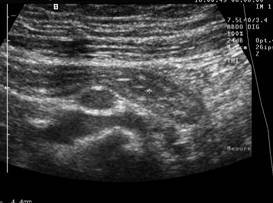

Compresia gradata sonografica este sugestiva pentru stabilirea cu acuratete a diagnsticului de apendicita. Apendicele apare ca o terminatie oarba, un fragment intestinal neperistaltic, cu originea la nivelul cecului. Printr-o compresiune maximala, se masoara diametrul antero-posterior al apendicelui. Testul este considerat pozitiv daca diametrul antero - posterior al apendicelui necomprimat este de 6 mm sau mai mult. Prezenta unui apendicolit stabileste diagnosticul. Imaginea ecografica a unui apendice normal, care este o structura tubulalara inchisa la un capat, usor compresibila, cu un diametru de 5 mm sau mai putin, exclude diagnosticul de apendicita acuta. Studiul este considerat negativ daca apendicele nu se vizualizeaza si nu exista o masa tumorala sau fluid pericecal. Cand se exclude ecografic diagnosticul de apendicita acuta, o scurta evaluare a restului cavitatii abdominale ar fi de preferat pentru stabilirea unui alt diagnostic. La femeile active sexual, organele pelvine genitale ar trebui vizualizate atat transabdominal, cat si transvaginal, pentru a exclude o patologie ginecologica care ar putea cauza durerea abdominala acuta.

Diagnosticul ecografic al apendicitei acute are o sensibilitate de 78 - 96 % si o specificitate de 85 - 98 %. Ecografia poate fi realizata in scop diagnostic la copii si femeile insarcinate, desi aplicabilitatea ei este oarecum limitata in ultimele luni de sarcina.

Ecografia are o serie de limite nete si rezultatele sunt dependente de experienta celui care o efectueaza. O imagine fals pozitiva poate sa apara in prezenta unui proces inflamator periapendicular determinat de inflamatia tesuturilor limitrofe; o dilatare a trompelor uterine poate fi confundata cu o inflamatie apendiculara, resturi de fecale neevacuate pot mima un apendicolit, iar la pacientii obezi, apendicele poate fi incompresibil atat datorita procesului inflamator acut, dar si datorita stratului de tesut adipos. Ecografii fals negative pot sa apara in conditiile unei limitari a procesului inflamator la varful apendicelui, in apendici cu localizare retrocecala, atunci cand este marit si poate fi confundat cu intestinul subtire sau in caz de perforatie apendiculara cand este comprimat.

Fig. 10 Apendicita acuta cu adenopatie inflamatorie